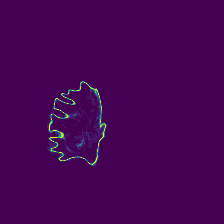

Diffusion models have shown impressive performance for generative modelling of images. In this paper, we present a novel semantic segmentation method based on diffusion models. By modifying the training and sampling scheme, we show that diffusion models can perform lesion segmentation of medical images. To generate an image specific segmentation, we train the model on the ground truth segmentation, and use the image as a prior during training and in every step during the sampling process. With the given stochastic sampling process, we can generate a distribution of segmentation masks. This property allows us to compute pixel-wise uncertainty maps of the segmentation, and allows an implicit ensemble of segmentations that increases the segmentation performance. We evaluate our method on the BRATS2020 dataset for brain tumor segmentation. Compared to state-of-the-art segmentation models, our approach yields good segmentation results and, additionally, detailed uncertainty maps.